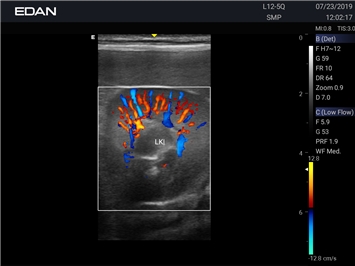

Ветеринарный ультразвук одним нажатием. Система Acclarix AX2 VET разработана с целью обеспечить бескомпромиссную производительность по доступной цене. Наличие уникальных двойных аккумуляторов в легком корпусе массой 4,5 кг из магниевого сплава позволяет системе Acclarix AX2 VET удовлетворять все потребности ветеринарных исследований, сохранив низкую стоимость.

EDAN Acclarix AX2 VET представляет собой специализированную ветеринарную ультразвуковую систему, сочетающую высокую производительность с доступной ценой. Благодаря продуманной конструкции и передовым технологиям, система обеспечивает качественную диагностику животных различных видов.

• Высокое разрешение для детальной диагностики

• Улучшенная визуализация глубоко расположенных органов

Цветовой допплер:

Да